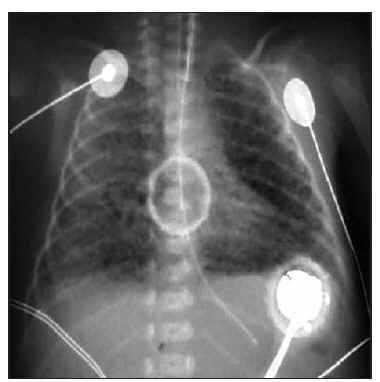

Recién nacida pretérmino, con edad gestacional de 27 + 5 semanas, peso al nacimiento 975 g (percentil 25), nacida por cesárea por desprendimiento de placenta. Precisó intubación al nacimiento, con un test de Apgar de 6/7 al minuto y 5 min de vida. Se administró la primera dosis de surfactante a los 20 min de vida, seguido de extubación precoz y colocación de presión positiva continua en vía aérea por vía nasal (CPAPn) bien toleradas. A las 27 h de vida necesitó reintubación por pausas de apnea y aumento del trabajo respiratorio; tras la radiología pulmonar se confirmó atelectasia bilateral y se administró una segunda dosis de surfactante, con lo cual mejoró de forma transitoria la oxigenación. En las siguientes horas, a pesar de ventilación mecánica convencional presentó hipoxemia e hipercapnia progresivas por lo que se inició ventilación de alta frecuencia oscilatoria (VAFO) a las 32 h de vida sin mejoría (fracción inspiratoria de oxígeno [FiO2] de 100 %, presión media en la vía aérea [PMA] 13 cmH2O, amplitud 100 %, 9 Hz), siendo la gasometría: pH, 7,17; presión parcial de dióxido de carbono (PCO2), 55 mmHg; presión parcial de oxígeno (PO2), 25 mmHg. En la radiografía de tórax se observa enfisema intersticial asimétrico y sobredistensión pulmonar (fig. 1). Tras la administración una tercera dosis de surfactante la hipoxemia se mantenía (presión parcial arterial de oxígeno [PaO2] en arteria umbilical de 30 mmHg), y a las 50 h de vida se decidió administrar ONi a 5 ppm, pero ante la falta de respuesta inicial, se aumentó transitoriamente la dosis (menos de 1 h) a 20 ppm, con lo que mejoraron los parámetros de oxigenación (PaO2 e índice de oxigenación) como puede observarse en la figura 2. El tratamiento con ONi se mantuvo 30 h y la paciente fue extubada a los 12 días de vida.

Figura 1. Caso 1. Radiografía de tórax que muestra enfisema intersticial asimétrico y sobredistensión pulmonar.